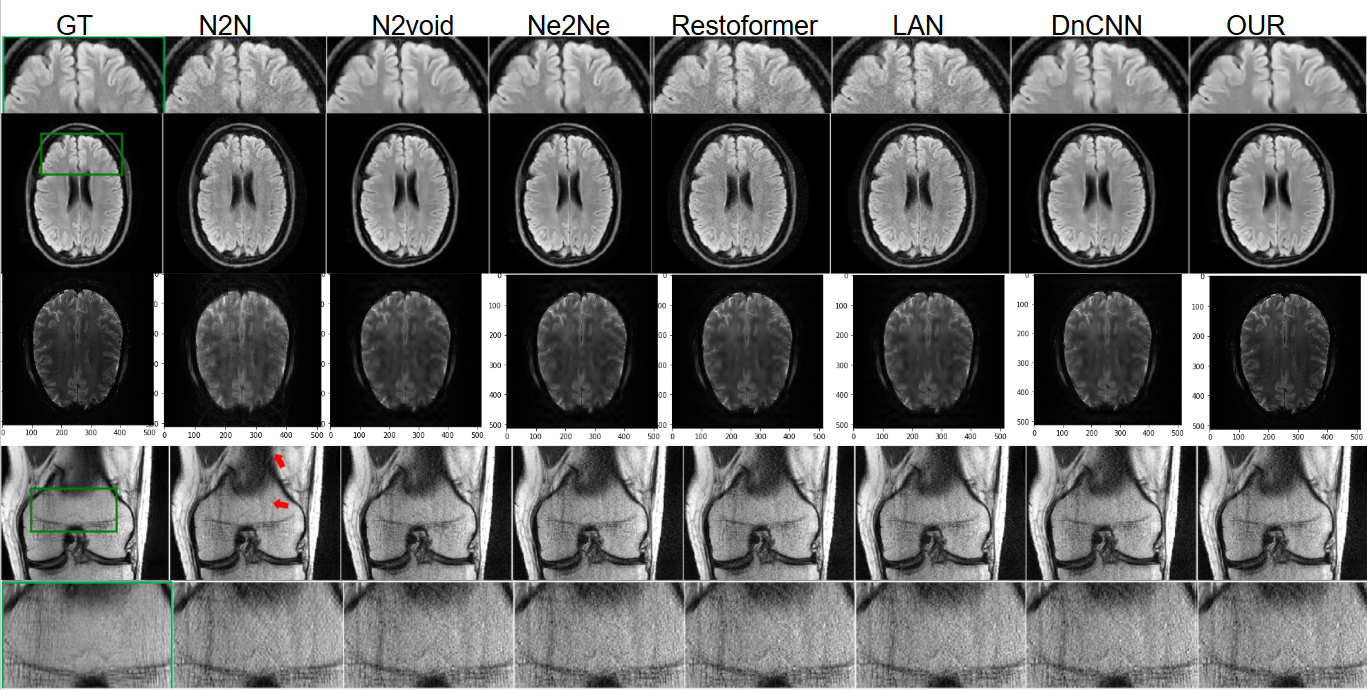

Refer to caption

Figure 3: (Top) AxFLAIR brain MRI, (Bottom) Cor-PD knee MRI; qualitative comparison of DnCNN [11], N2N [7], Ne2Ne [4], Restoformer [10], N2void [6], LAN [5], and our method. First column represent ground truth image.

Qualitative Comparisons. We show in Figs 4 and 3 to show the qualitative comparison of our images. From the enlarged view of Fig. 3, it is not difficult to find that the image reconstructed by DnCNN [11], N2N [7], Ne2Ne [4], Restoformer [10], N2void [6], LAN [5] methods. Fig. 3 shows the denoising results of trained models on a noise pattern σ=15𝜎15\sigma=15italic_σ = 15, see first image of the second row in Fig. 3. The experimental results are consistent with the above experimental performance, which further verifies the robustness of our method in terms of noise pattern.